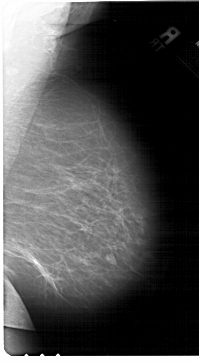

ics_version 1.0 filename A-1567-1 DATE_OF_STUDY 7 6 1995 PATIENT_AGE 44 FILM FILM_TYPE REGULAR DENSITY 2 DATE_DIGITIZED 2 10 1998 DIGITIZER HOWTEK 43.5 SEQUENCE LEFT_CC LINES 6871 PIXELS_PER_LINE 3841 BITS_PER_PIXEL 12 RESOLUTION 43.5 OVERLAY LEFT_MLO LINES 6871 PIXELS_PER_LINE 4051 BITS_PER_PIXEL 12 RESOLUTION 43.5 OVERLAY RIGHT_CC LINES 6841 PIXELS_PER_LINE 3841 BITS_PER_PIXEL 12 RESOLUTION 43.5 NON_OVERLAY RIGHT_MLO LINES 6871 PIXELS_PER_LINE 3781 BITS_PER_PIXEL 12 RESOLUTION 43.5 NON_OVERLAY |